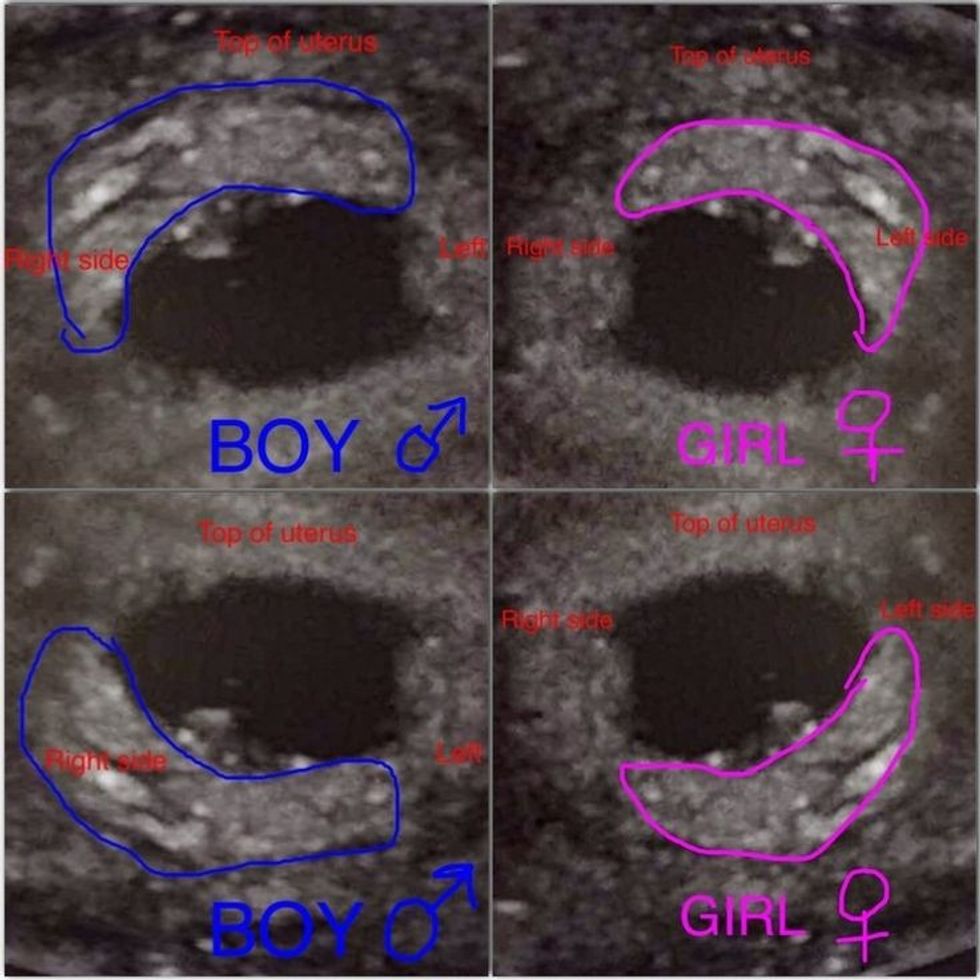

Teoria e Ramzi-t sugjeron se vendndodhja e placentës në barkun e nënës mund të tregojë nëse foshnja është djalë apo vajzë.

Nëse placenta zhvillohet në anën e djathtë të mitrës, sipas teorisë, ka më shumë gjasa të jetë djalë, ndërsa nëse është në të majtën, ka mundësi të jetë vajzë.